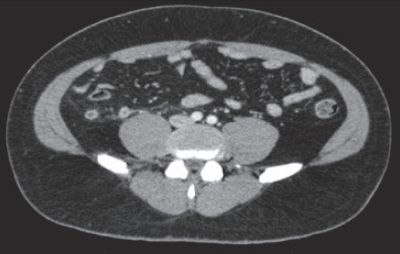

血液所見:赤血球486万、Hb 15.2g/dL、Ht 43%、白血球16,200、血小板24万。血液生化学所見:総蛋白6.4g/dL、アルブミン4.2g/dL、総ビリルビン0.7mg/dL、AST 23U/L、ALT 18U/L、LD 147U/L(基準120~245)、尿素窒素20mg/dL、クレアチニン0.9mg/dL。CRP 0.9mg/dL。腹部超音波検査では病変の描出が不明瞭であった。腹部造影CTの横断像と斜冠状断像を別に示す。